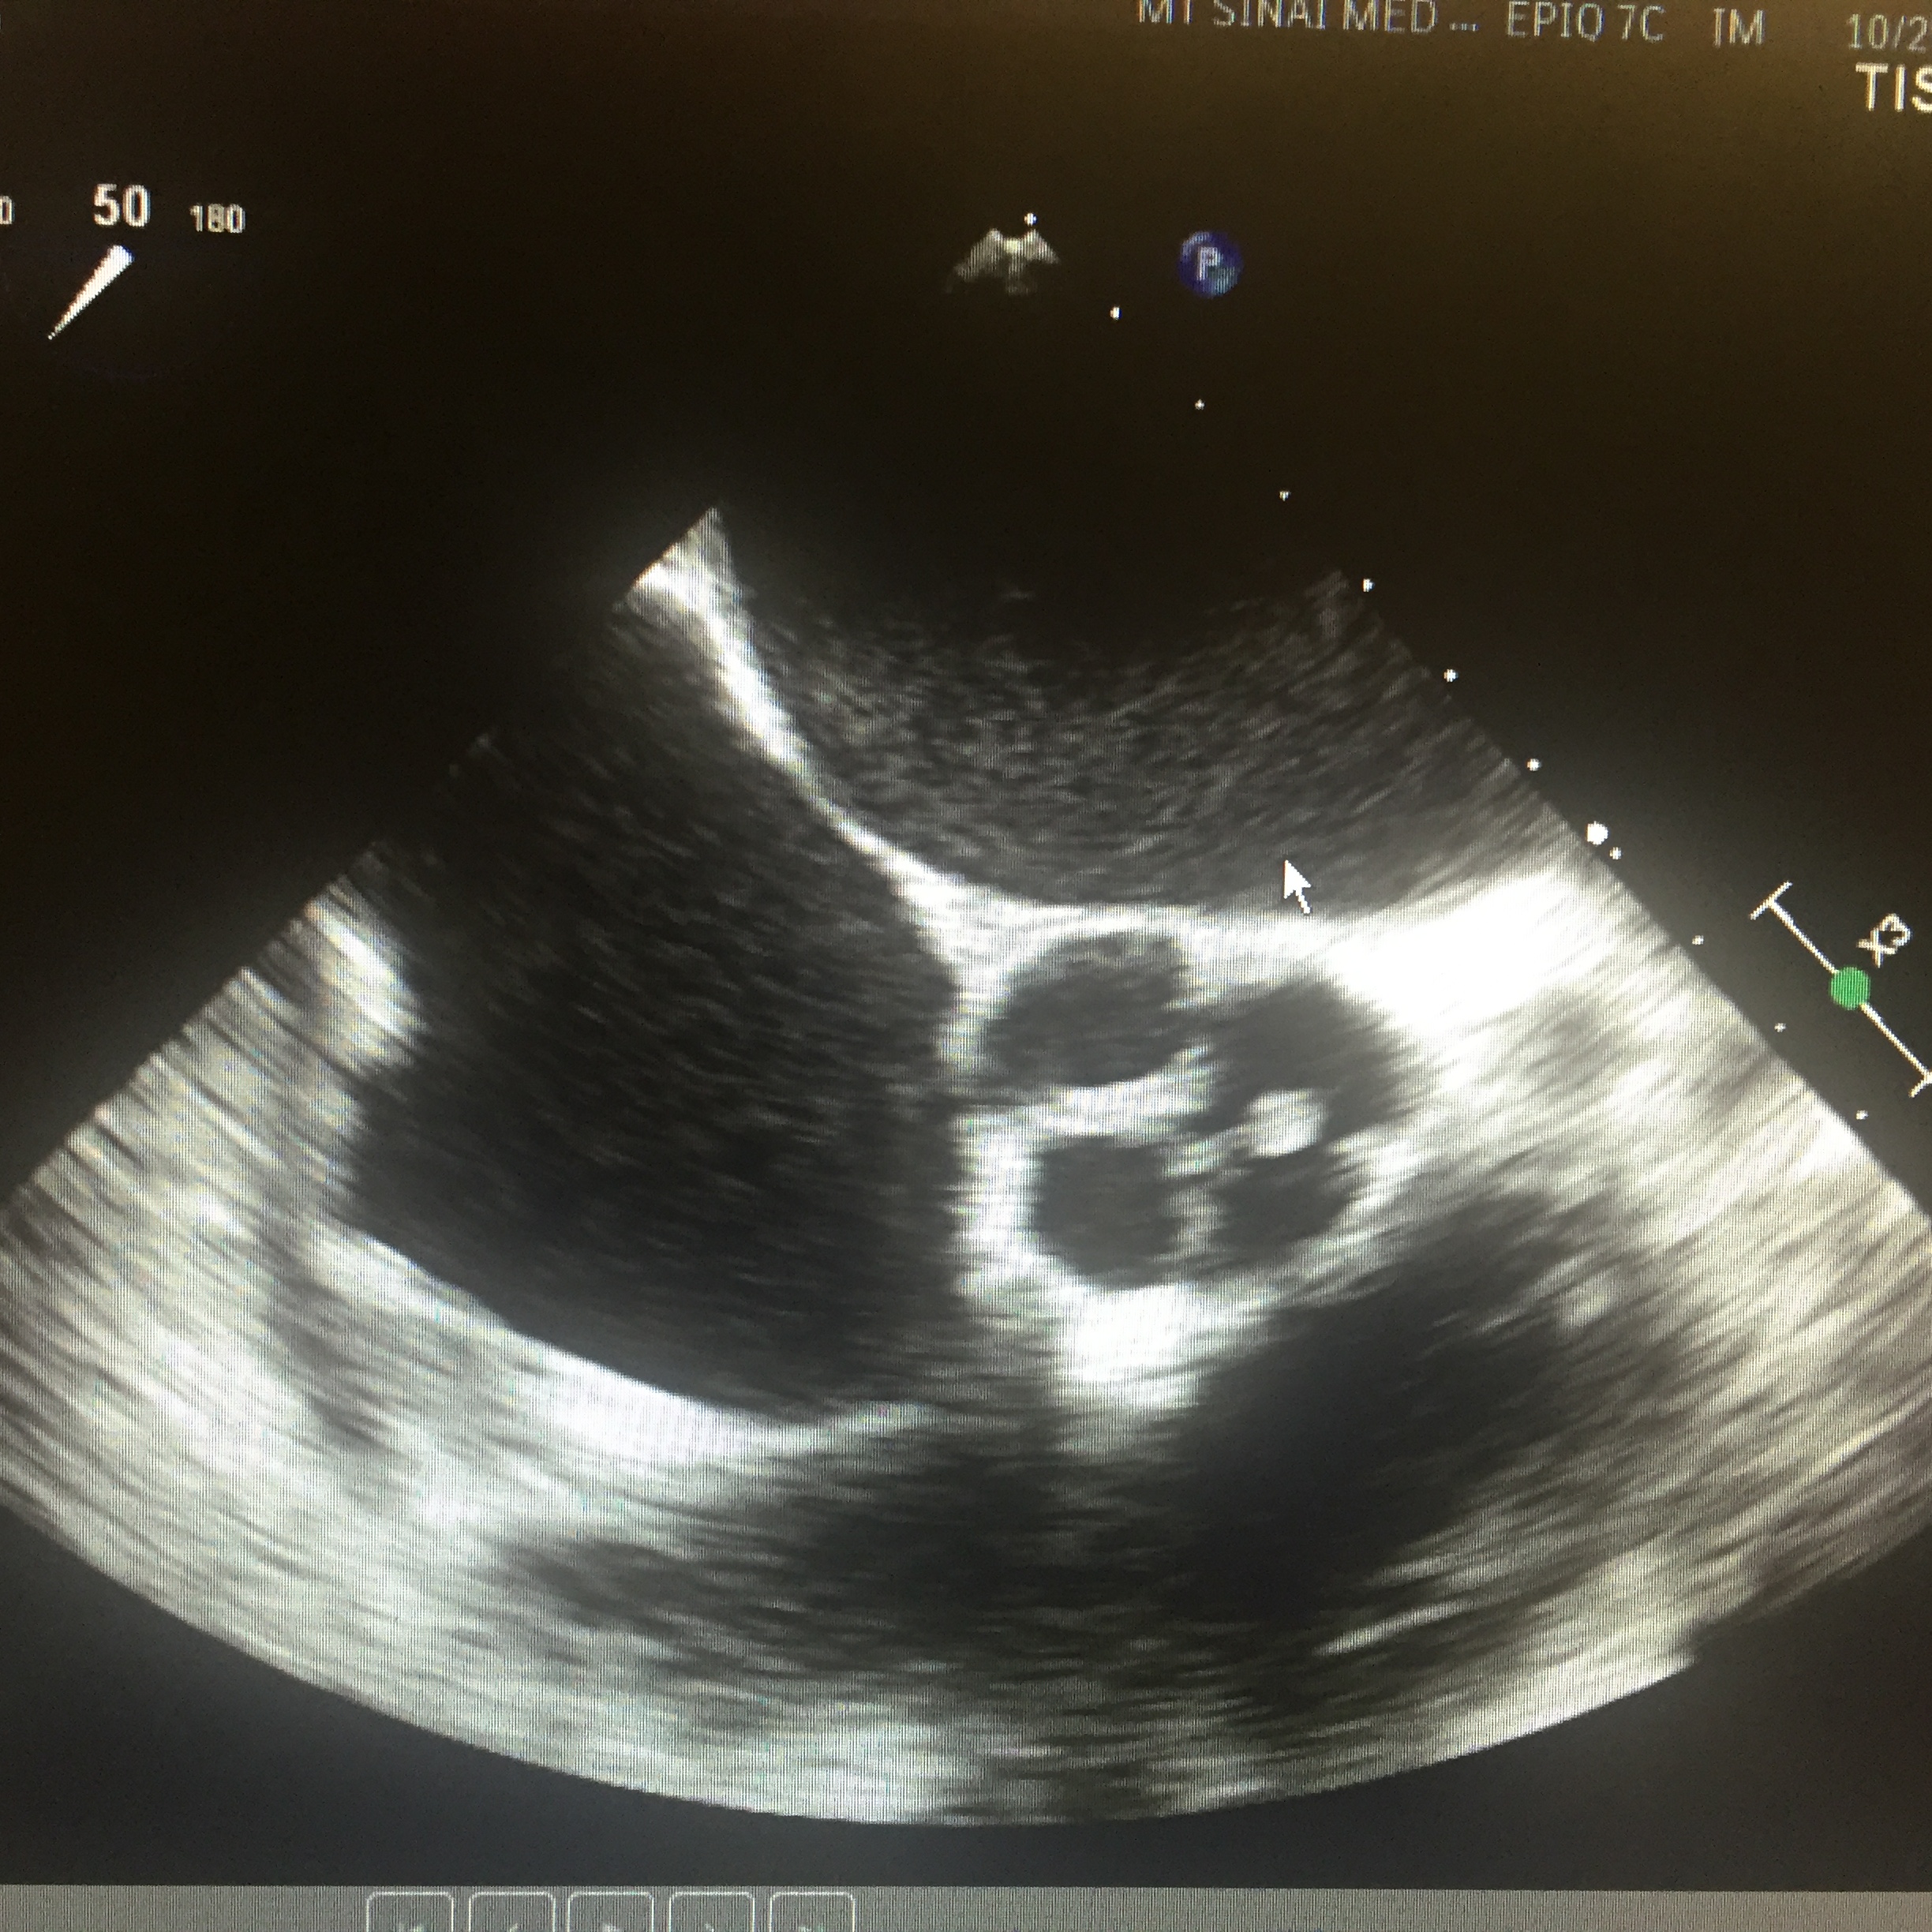

IMAGE 1: A Quadricuspid Aortic Valve

IMAGE 2: A Quadricuspid Aortic Valve

Case Presentation: A 49-year-old male presented with progressive lower extremity edema, exertional dyspnea and orthopnea for three weeks. Past medical history significant for non-ischemic cardiomyopathy, systolic heart failure and moderate aortic regurgitation (AR) diagnosed one year ago. Physical exam was significant for jugular vein distention, bibasilar crackles, loud 3/6 diastolic murmur in the aortic area with bilateral lower extremities edema. Chest x-ray revealed pulmonary congestion. Transthoracic echo showed worsening of his existing left ventricular ejection fraction (LVEF) from 30-35% one year before to 25-20%, global hypokinesis, and worsening AR. In an effort to further explain his rapid progressing heart failure and AR, the patient underwent transesophageal echo (TEE) and coronary angiogram after finishing his treatment for acutely decompensated heart failure. TEE revealed quadricuspid aortic valves with partial fusion of leaflets resulting in functionally bicuspid valve with incomplete coaptation of the leaflets with a resultant central gap. Aorta was mildly dilated measuring 4.1 cm at the level of ascending aorta. Coronary angiogram showed non-obstructive coronary arteries without anomalies. The patient is then referred for surgical aortic valve replacement and is currently waiting for surgical aortic valve replacement.